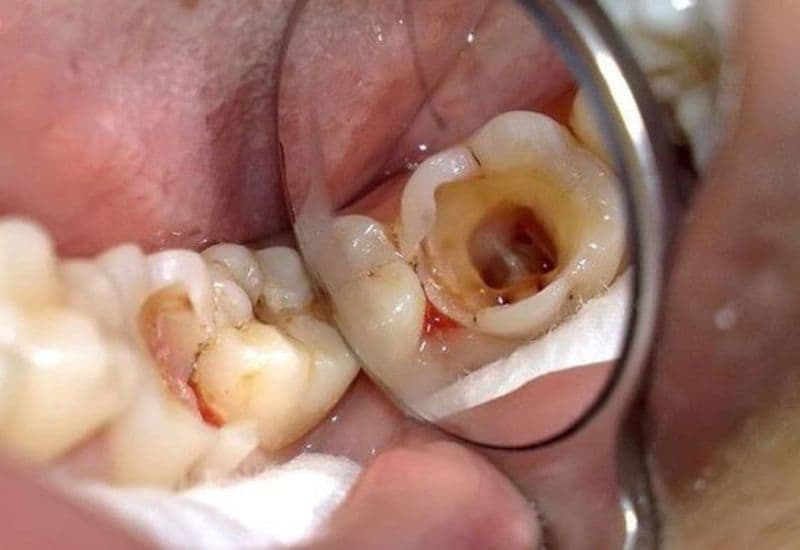

Sâu răng tủy là giai đoạn nặng nhất của bệnh sâu răng, khi vi khuẩn đã xâm nhập qua các lớp men răng, ngà răng và tiến sâu vào buồng tủy. Tủy răng chứa các mạch máu, dây thần kinh và các mô liên kết khác, đóng vai trò quan trọng trong việc nuôi dưỡng và bảo vệ răng. Khi tủy răng bị tổn thương, người bệnh thường cảm thấy đau đớn dữ dội và cần được điều trị ngay lập tức.

– Lỗ sâu có thể nhìn thấy: Xuất hiện lỗ hổng hoặc hố sâu trên bề mặt răng.